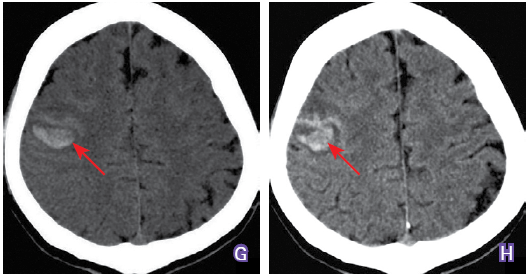

走错路正常细菌秒变恶魔丨卒中杂谈第9期

图片尺寸528x276